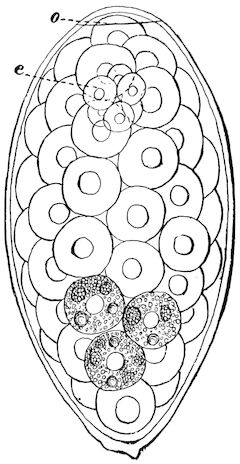

Fig. 1.—Rachitis in a young goat.